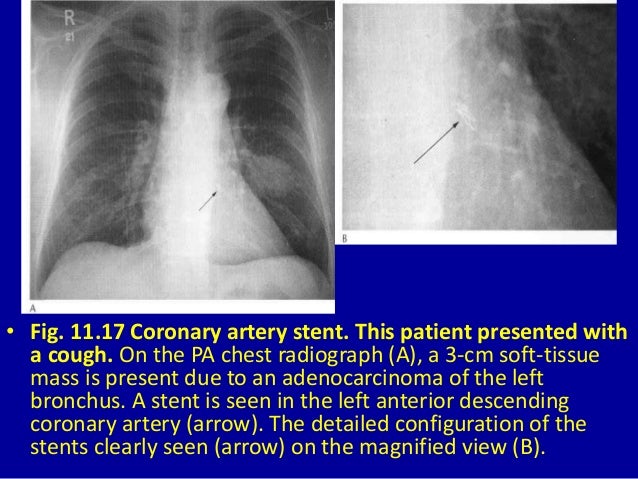

Chapter 3 Imaging Of The Heart And Great Vessels Radiology Key

radiologykey.com